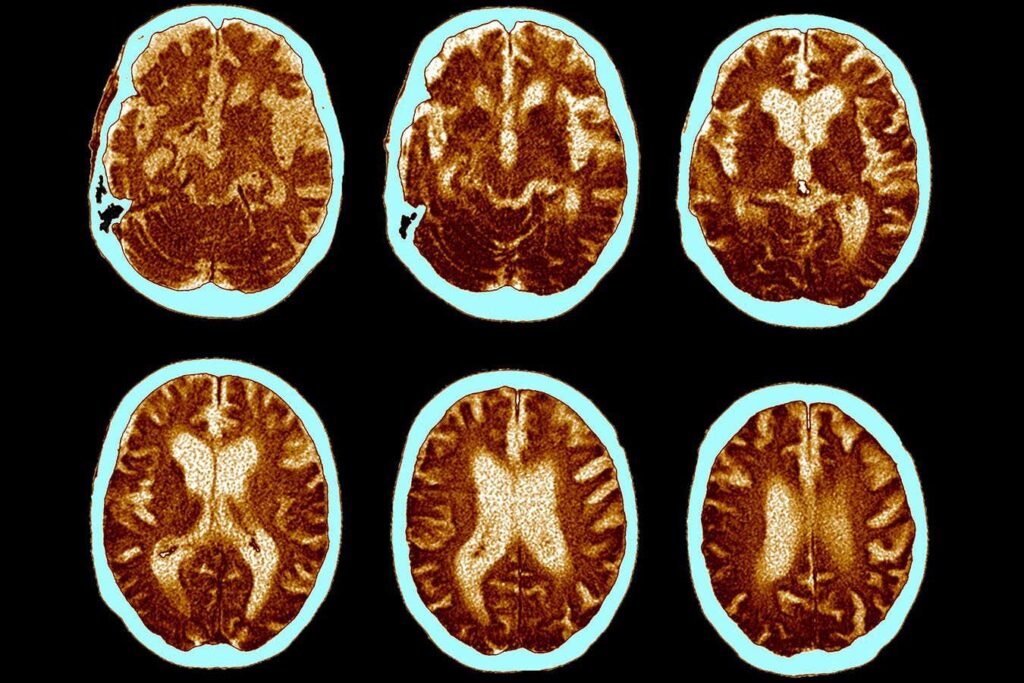

The brain shrinkage seen in Alzheimer’s can be prevented with semaglutide, the drug in Ozempic.

ZEPHYR/Science Photo Library/Alamy